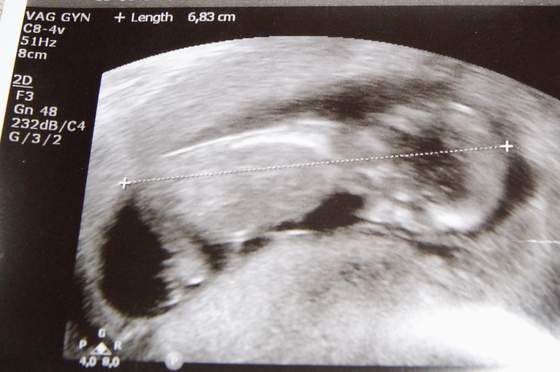

USG ok, dziecko bardzo się ruszało , długo musiał naciskać i wogóle żeby pokazało nosek, tą bruzdę karkową i coś tam jeszcze....

jakoś wydaje mi się że inni lekarze robią bardziej szczegółowe te USG ale może się myle, lekarz powiedział, że na tym etapie ciąży wszystko w porządku, żadnych wad genetycznych nie uwidoczniono,

aaaaaaaaaaa i pokazało co na 90% ma między nogami, raczej będzie druga baba hhahahah, czas pokaże może to się zmieni, ale jest mi tak wszystko jedno że szok, mąż jakoś też to przyjął ze śmiechem, aby zdrowe było, a tak w sumie, Oliwia będzie miała siostrę, może to fajniej nawet dla niej... sama nie wiem, nno i ogromny plus że dużo rzeczy po Oliwi będzie hihi, a ja właściwie nie liczyłam na chłopca, cały czas myślałam aby zdrowe, no i niech będzie baba a co tam,